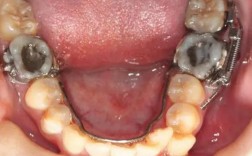

部分患者存在磨牙扭转(如上颌第一磨牙近中颊尖旋转)或倾斜(如磨牙近中倾斜导致咬合紊乱),此时需通过绞钢丝进行“微调”,对于扭转的磨牙,医生可采用“8字结扎”:用一段绞钢丝穿过磨牙托槽的翼部,与邻牙托槽交叉结扎,通过交叉产生的扭转力,逐渐将旋转的牙齿纠正至正常位置;对于倾斜的磨牙,则可通过“垂直结扎”(将钢丝从托槽垂直方向结扎)或“水平结扎”(从水平方向结扎),调整牙齿的倾斜角度,确保咬合接触点均匀。